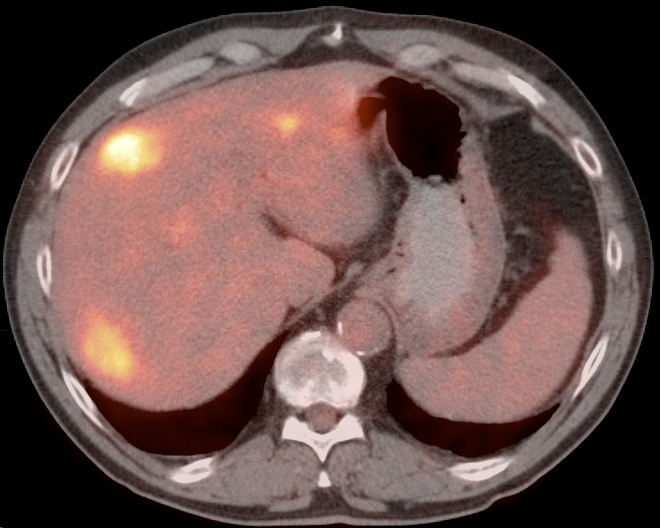

The most common sites of metastatic disease include the lymph nodes (regional & distant), liver, lung, peritoneal cavity, bones, brain and adrenal glands.